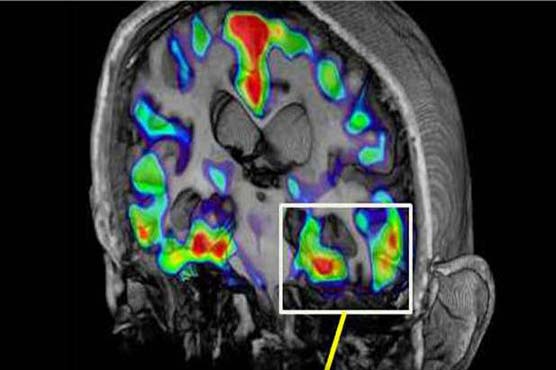

Researchers tested the drug s effect on a protein named beta-amyloid that in Alzheimer s, somehow goes awry and forms gunky brain plaques. First researchers gave the drug to older mice and their plaques quit growing. Then they gave a single dose to a small group of healthy young adults and their bodies normal production of amyloid dropped.